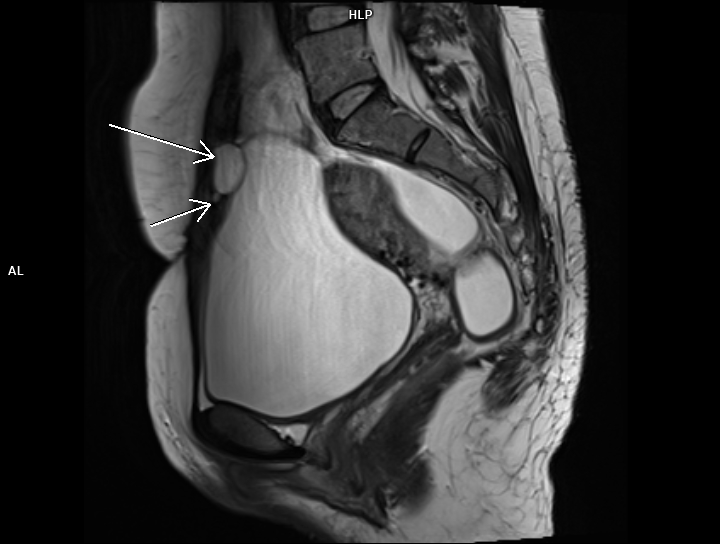

Figura 2: sagital T2

Discuţie caz nr 83: chistul de uracă apare datorită faptului ca uraca nu s-a inchis complet în timpul dezvoltării fetale si este un buzunar umplut cu lichid; uraca este o structură embriologică normală care leagă vezica fetală de cordonul ombilical. Majoritatea chistelor uracale sunt asimptomatice, însă uneori se pot infecta şi pot provoca complicații: simptome ale tractului urinar, hematurie sau o masă palpabilă.

Chistele de uraca se datorează faptului că uraca nu s-a închis în primul trimestru de sarcina; pot fi descoperiri întâmplătoare la examinările imagistice sau se pot complica.